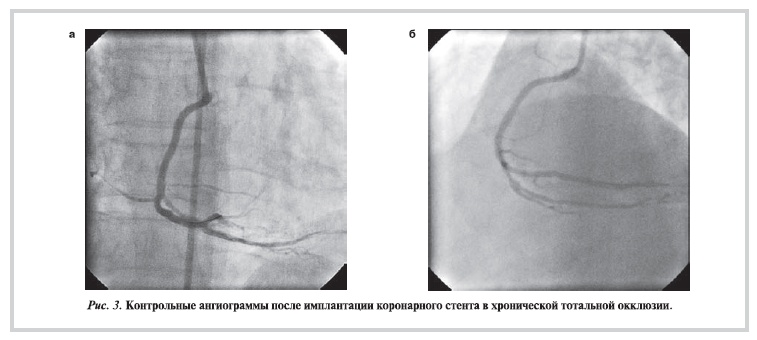

После проведения реканализации ХТО коронарным проводником формировали канал пенетрационным катетером, который вращали вручную. В 81,4% случаев Tornus был успешно проведен в дистальное русло коронарной артерии. Еще у 8 (18,6%) пациентов с выраженным кальцинозом ХТО не удалось провести пенетрационный катетер дистальнее окклюзии, но частично сформированный канал

в ХТО позволил в 2 случаях завести в поражение коронарный баллон и выполнить последующую успешную баллонную ангиопластику и имплантировать коронарный стент. Пример успешной реканализации ХТО правой коронарной артерии представлен ниже (рис. 1—3).

Рисунок 3. Контрольные ангиограммы после имплантации коронарного стента в хронической тотальной окклюзии.